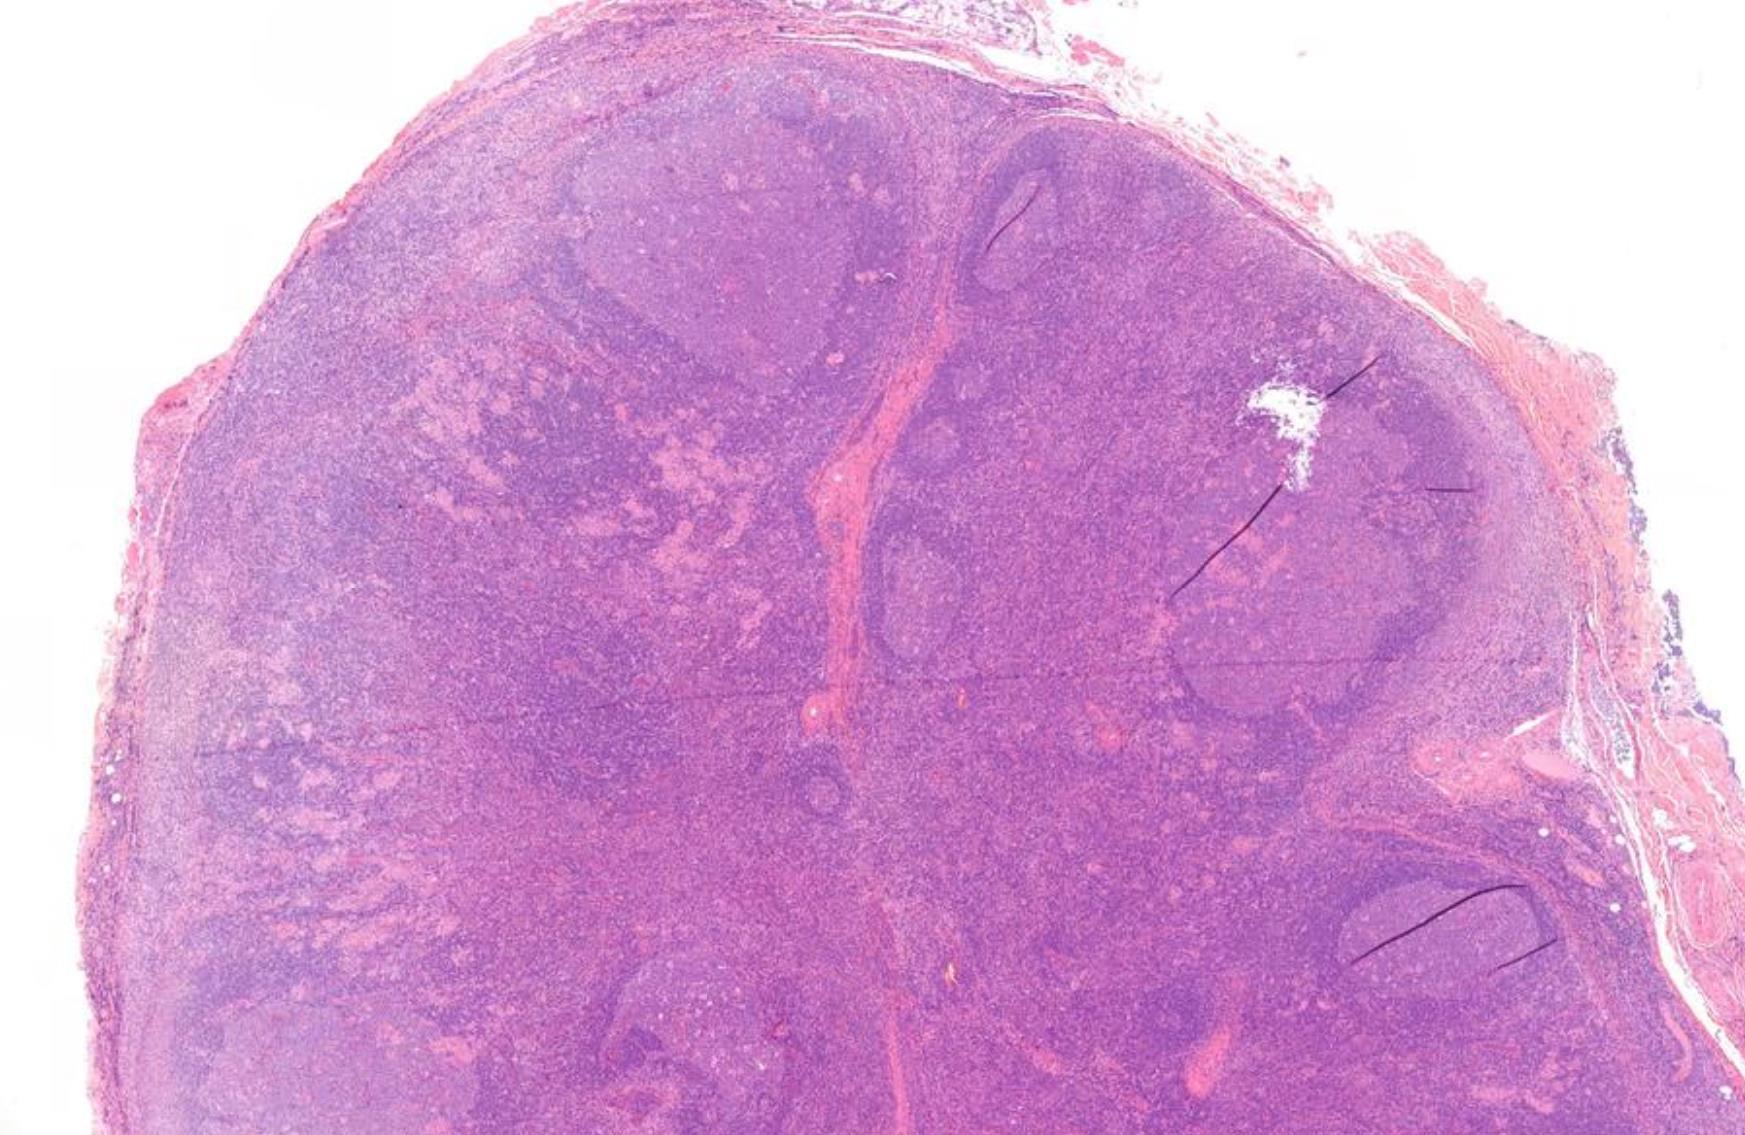

Male 64 years, Left parotid gland mass.

??

Case 19 Diagnosis

Extranodal marginal zone lymphoma (MALT)

•H&N 2nd most common site after GI tract •Small lymphocytes and marginal zone cells •Monocytoid cells with abundant pale cytoplasm are sometimes present •Remnants of reactive follicles are

sometimes with follicular colonization.

formed lymphoepithelial lesions

common,

Well-

• Positive for CD20, CD22, PAX5), usually IgM, occasionally IgG or IgA, and rarely IgD, CD43 or TBX21 (T-bet)

• Negative for CD5, CD10, BCL6, CD23, cyclin D1, SOX11, and EBV

• Immunoglobulin light chain monotypia of B cells or plasma cells